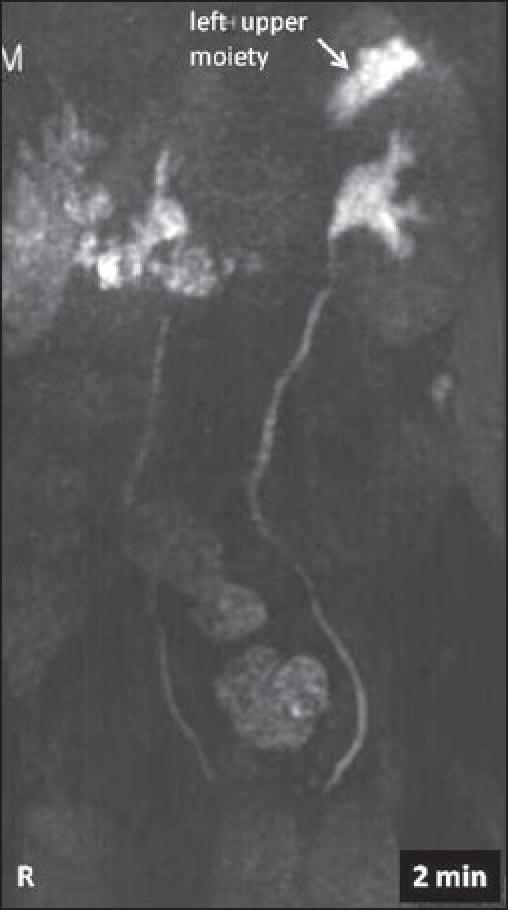

This is a report on the use of magnetic resonance urography (MRU) in a 6-year-old girl who presented with urinary incontinence. She had a left duplex kidney with poorly functioning upper moiety and ectopic insertion of the dilated upper pole ureter. MRU has been shown to be superior to conventional imaging techniques in delineating poorly functioning moieties of duplex kidneys and ectopic ureters.

这是一份关于一名6岁患尿失禁女童的磁共振尿路造影(MRU)应用报告。她患有左侧重复肾,上半部分功能不佳,扩张的上极输尿管异位开口。在描绘重复肾功能不佳的部分和异位输尿管方面,MRU已被证明优于传统成像技术。